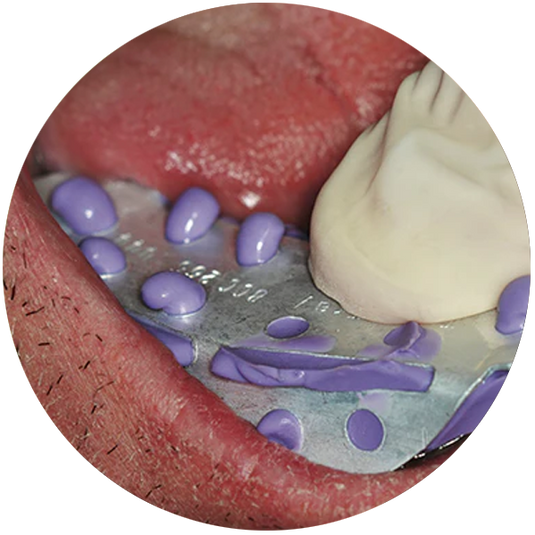

Posterior Matrix Solutions

Are there times when you were surprised by a loose or open contact when you finished a Class II restoration? Do you ever see a funnel shape to your Class II composites on an x-ray? What if there wa...